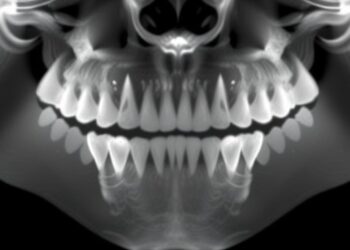

TriGWONet: Efficient Oral Cancer Detection via AI

In an era where artificial intelligence is profoundly influencing various sectors, a groundbreaking approach to oral cancer detection is generating ...